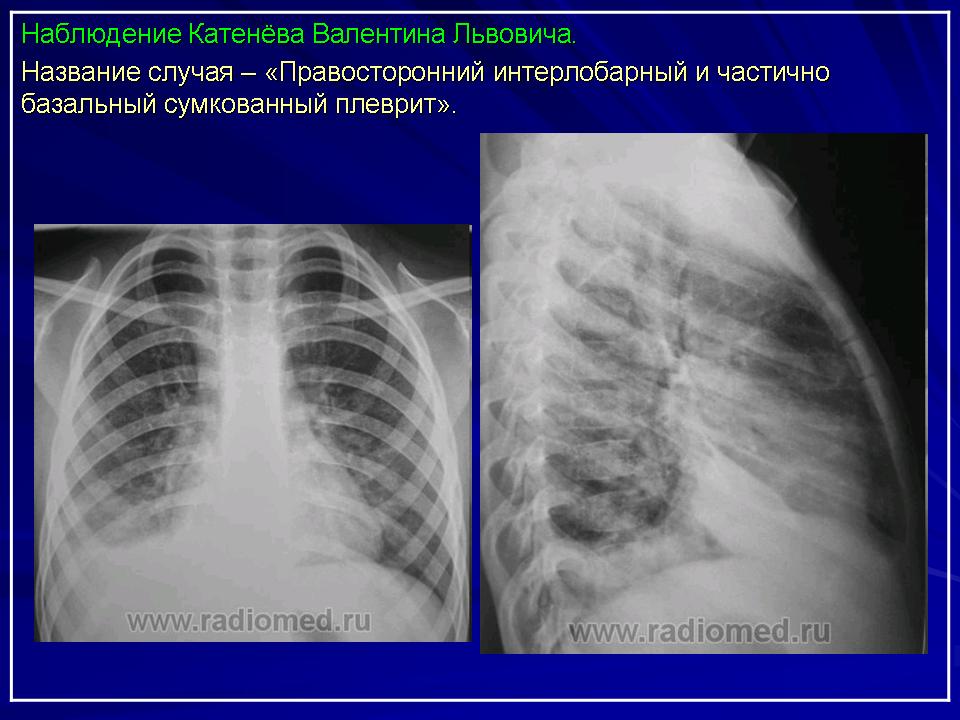

Плевральный выпот в большей или меньшей степени отражается как на дыхании, так и кровообращении. При постепенном скоплении жидкости и спадении легкого одышка выражена слабо. При быстро развивающемся массивном выпоте одышка может оказаться сильной и сопровождаться цианозом. Туберкулиновые пробы преимущественно нормергические. При рассасывании экссудата покрытые фибрином и утолщенные листки плевры часто сращиваются один с другим. В некоторых случаях от плевры к легкому тянутся соединительно-тканные спайки. Таким образом, может развиться плеврогенный пневмосклероз. Легкое в таком случае остается на продолжительное время спавшим и с уменьшенным содержанием воздуха. После излечения процесса формируются остаточные изменения в виде утолщений реберно-диафрагмальной, междолевой плевры и заращений синусов. Утолщения плевры (шварты) могут достигать значительной толщины и протяженности, что зависит от того, сколько осумковалось жидкости и какая ее часть подверглась затем процессу фибринизации (рис. 7, 8).

Лучевая диагностика. Рентгенологическое обследование в диагностике плеврального синдрома занимает ведущее место. Рентгенологическая картина свободного выпота, когда объем жидкости увеличивается, характеризуется затемнением наружного костно-диафрагмального синуса, части легочного поля над куполом диафрагмы с косой верхней границей тени, что и позволяет предполагать наличие плевральной жидкости уже по обзорной рентгенограмме. Важным элементом обследования является определение признаков свободного растекания жидкости в плевральной полости, для чего применяется латерография. Латерограммы, выполненные одновременно на вдохе и выдохе, позволяют судить о количестве свободно перемещающейся жидкости. Как известно, при туберкулезном плеврите экссудат довольно быстро может подвергаться организации (фибринизации), отграничению или осумкованию. При средних и больших объемах выпота выявить эти признаки возможно лишь при латерографии на больном и здоровом боку, а также при УЗИ и КТ, что полностью подтверждено при сопоставлении этих картин при визуальном торакоскопическом контроле УЗИ и КТ особенно важны при осумкованных плевритах. УЗИ может обнаружить 5 мл плевральной жидкости.